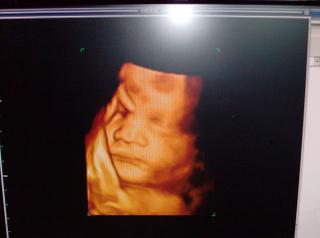

mne doktor tak povedal..to ze absolvujete amnioa vyjde vsetko ok..vam este nazaruci , ze porodite zdrave dietatko..pri porode sa moze stat vsetko...ja som tomu doktorovi velmi verila, ukazal mi matka na ultrazvuku s kazdej strany, pocitali sme palceky, meral mu co merat mal..pri dawne su urcite veci, ktoore by sa mali ukazat..skratene prsteky, mozog, ..a vsetky merania boli ok..a potom ked ten 4D ultrazvuk je nieco tak nadherne, babo tam je ako v skutocnosti..a bola to laska na prvy pohlad 😀 ...prajem ti